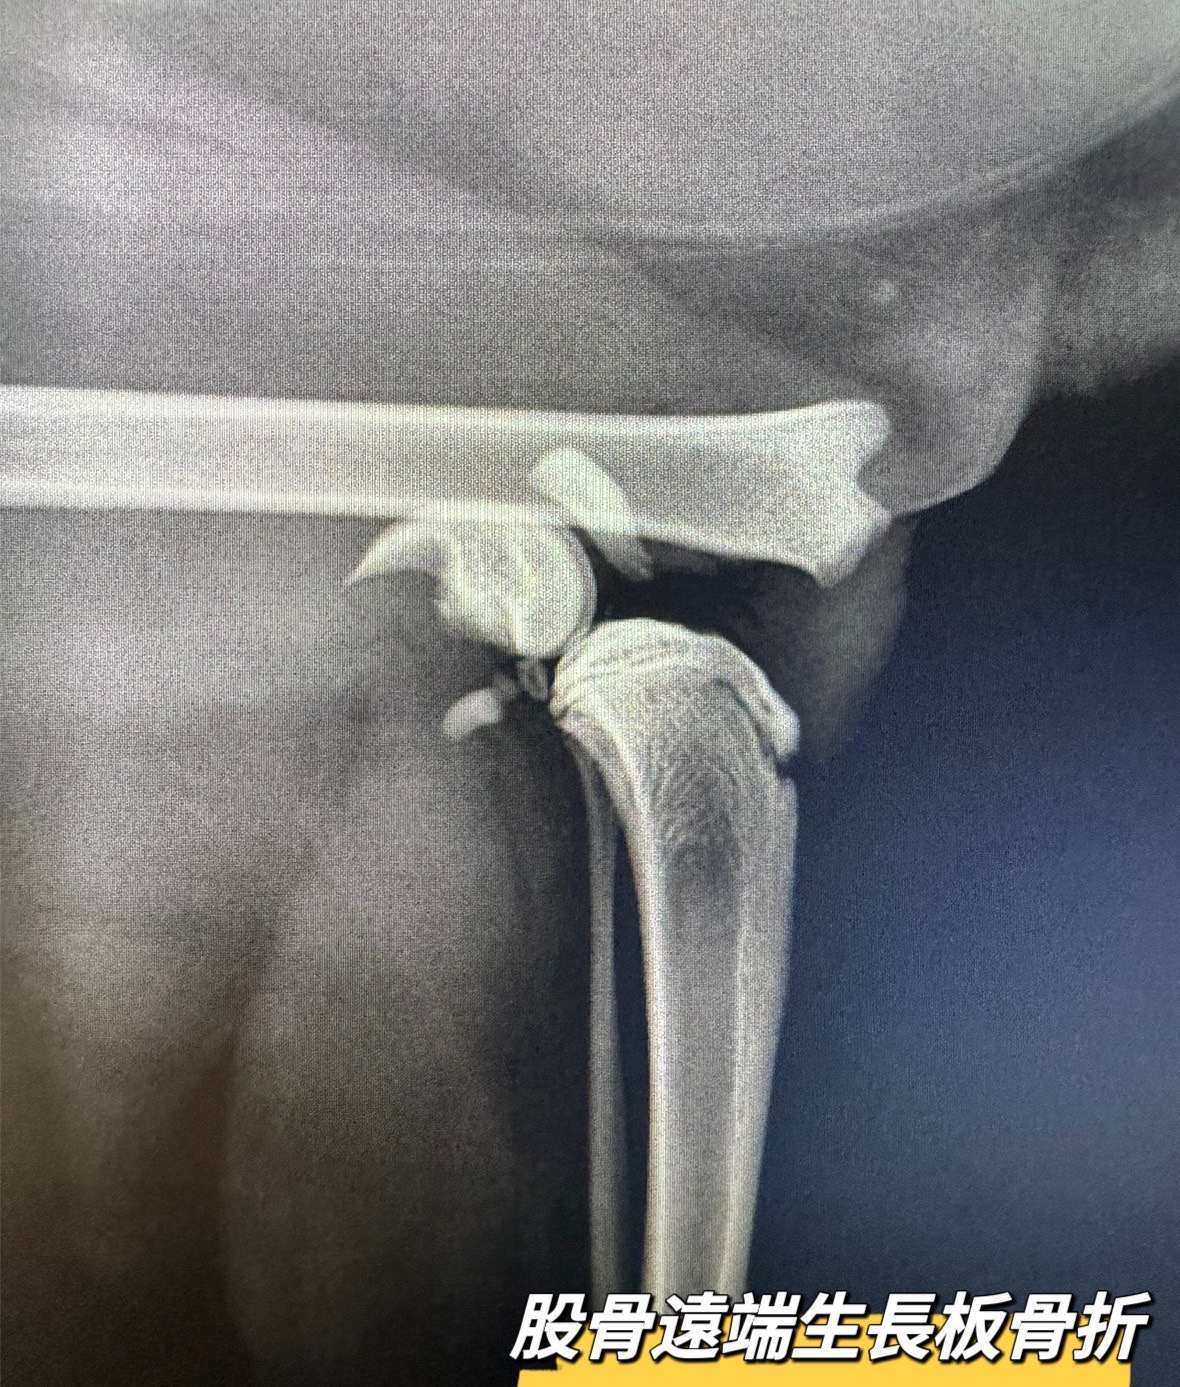

股骨遠端生長板骨折

五個月大的橘橘

充滿活力

每天跳上跳下

一天當主人回到家時,卻不見平常活蹦亂跳的橘橘

這才發現橘橘躲在角落一臉驚恐樣

就醫透過

#x光檢查

發現是

#股骨遠端生長板骨折

不知道橘橘在家發生了什麼事…

所幸經過手術復位固定後,骨頭很快的癒合‼️

【股骨遠端生長板骨折】

幼年動物特有的骨折方式

主要發生在生長板尚未關閉的年輕動物

一般透過骨釘即可提供穩定固定

幼年動物骨頭癒合快速

需把握黃金期,盡早治療